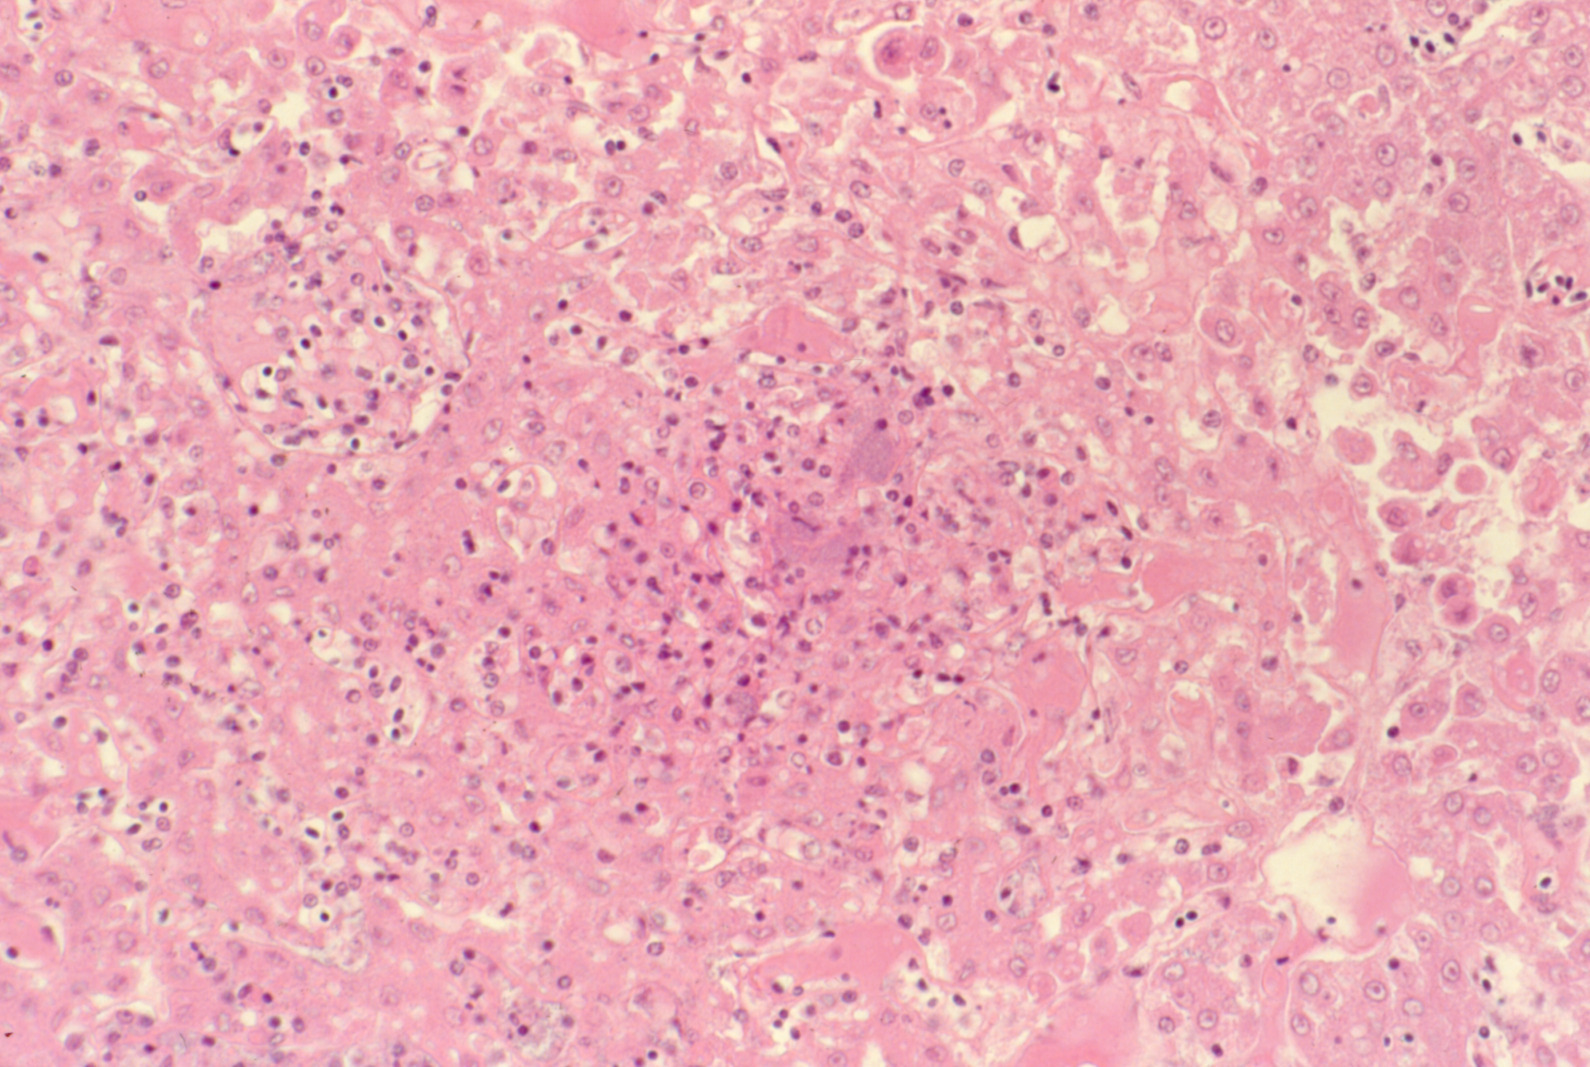

Fowl cholera (slide study set no. 19) Item Info

Fowl cholera (slide study set no. 19)

Poultry--Diseases Chicken cholera